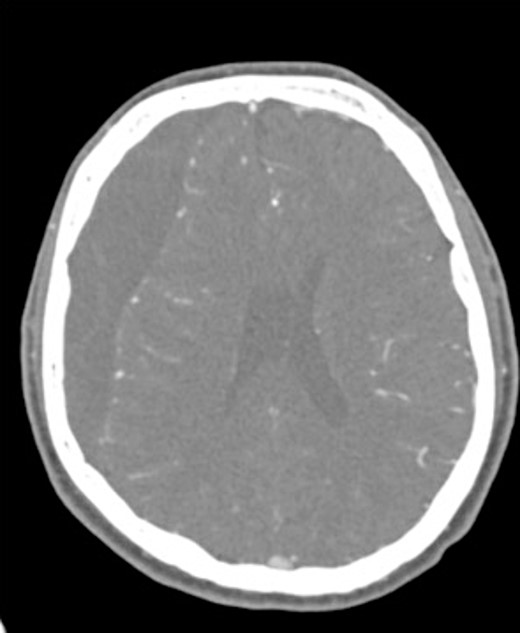

An 81-year-old male with a history of acute subdural hematoma, previously managed non-surgically, presented with worsened confusion and cognitive dysfunction. Repeat CT demonstrated expansion of right-sided subdural collection, consistent with cSDH (Fig. 4).

After the head was positioned in a supine neutral position on a horseshoe head holder, the AR system was used to overlay the hematoma and other relevant anatomy onto the patient’s head. Midline locations, vasculature and the blood collection were appreciated via AR overlay prior to marking an incision (Fig. 5). The AR overlay was then used to plan two separate linear incisions for two right-sided burr holes—one frontal and one parietal over the largest components of the hematoma as visualized with AR. A perforator drill was used to create the two burr holes which were widened with a burr and rongeurs. Beneath the dura, a hematoma was identified and its thick membrane layer was coagulated with bipolar cautery. The surgical sites were irrigated with saline to evacuate chronic blood. A ventriculostomy catheter was then placed into the subdural space at the frontal burr hole and tunneled lateral to the incisions. The burr holes were covered with titanium covers. There were no intraoperative complications, and the tolerated procedure well with improved cognitive function several days after surgery. Post-operative CT demonstrated significant interval decrease in hematoma volume and reduction in midline shift (Fig. 6).